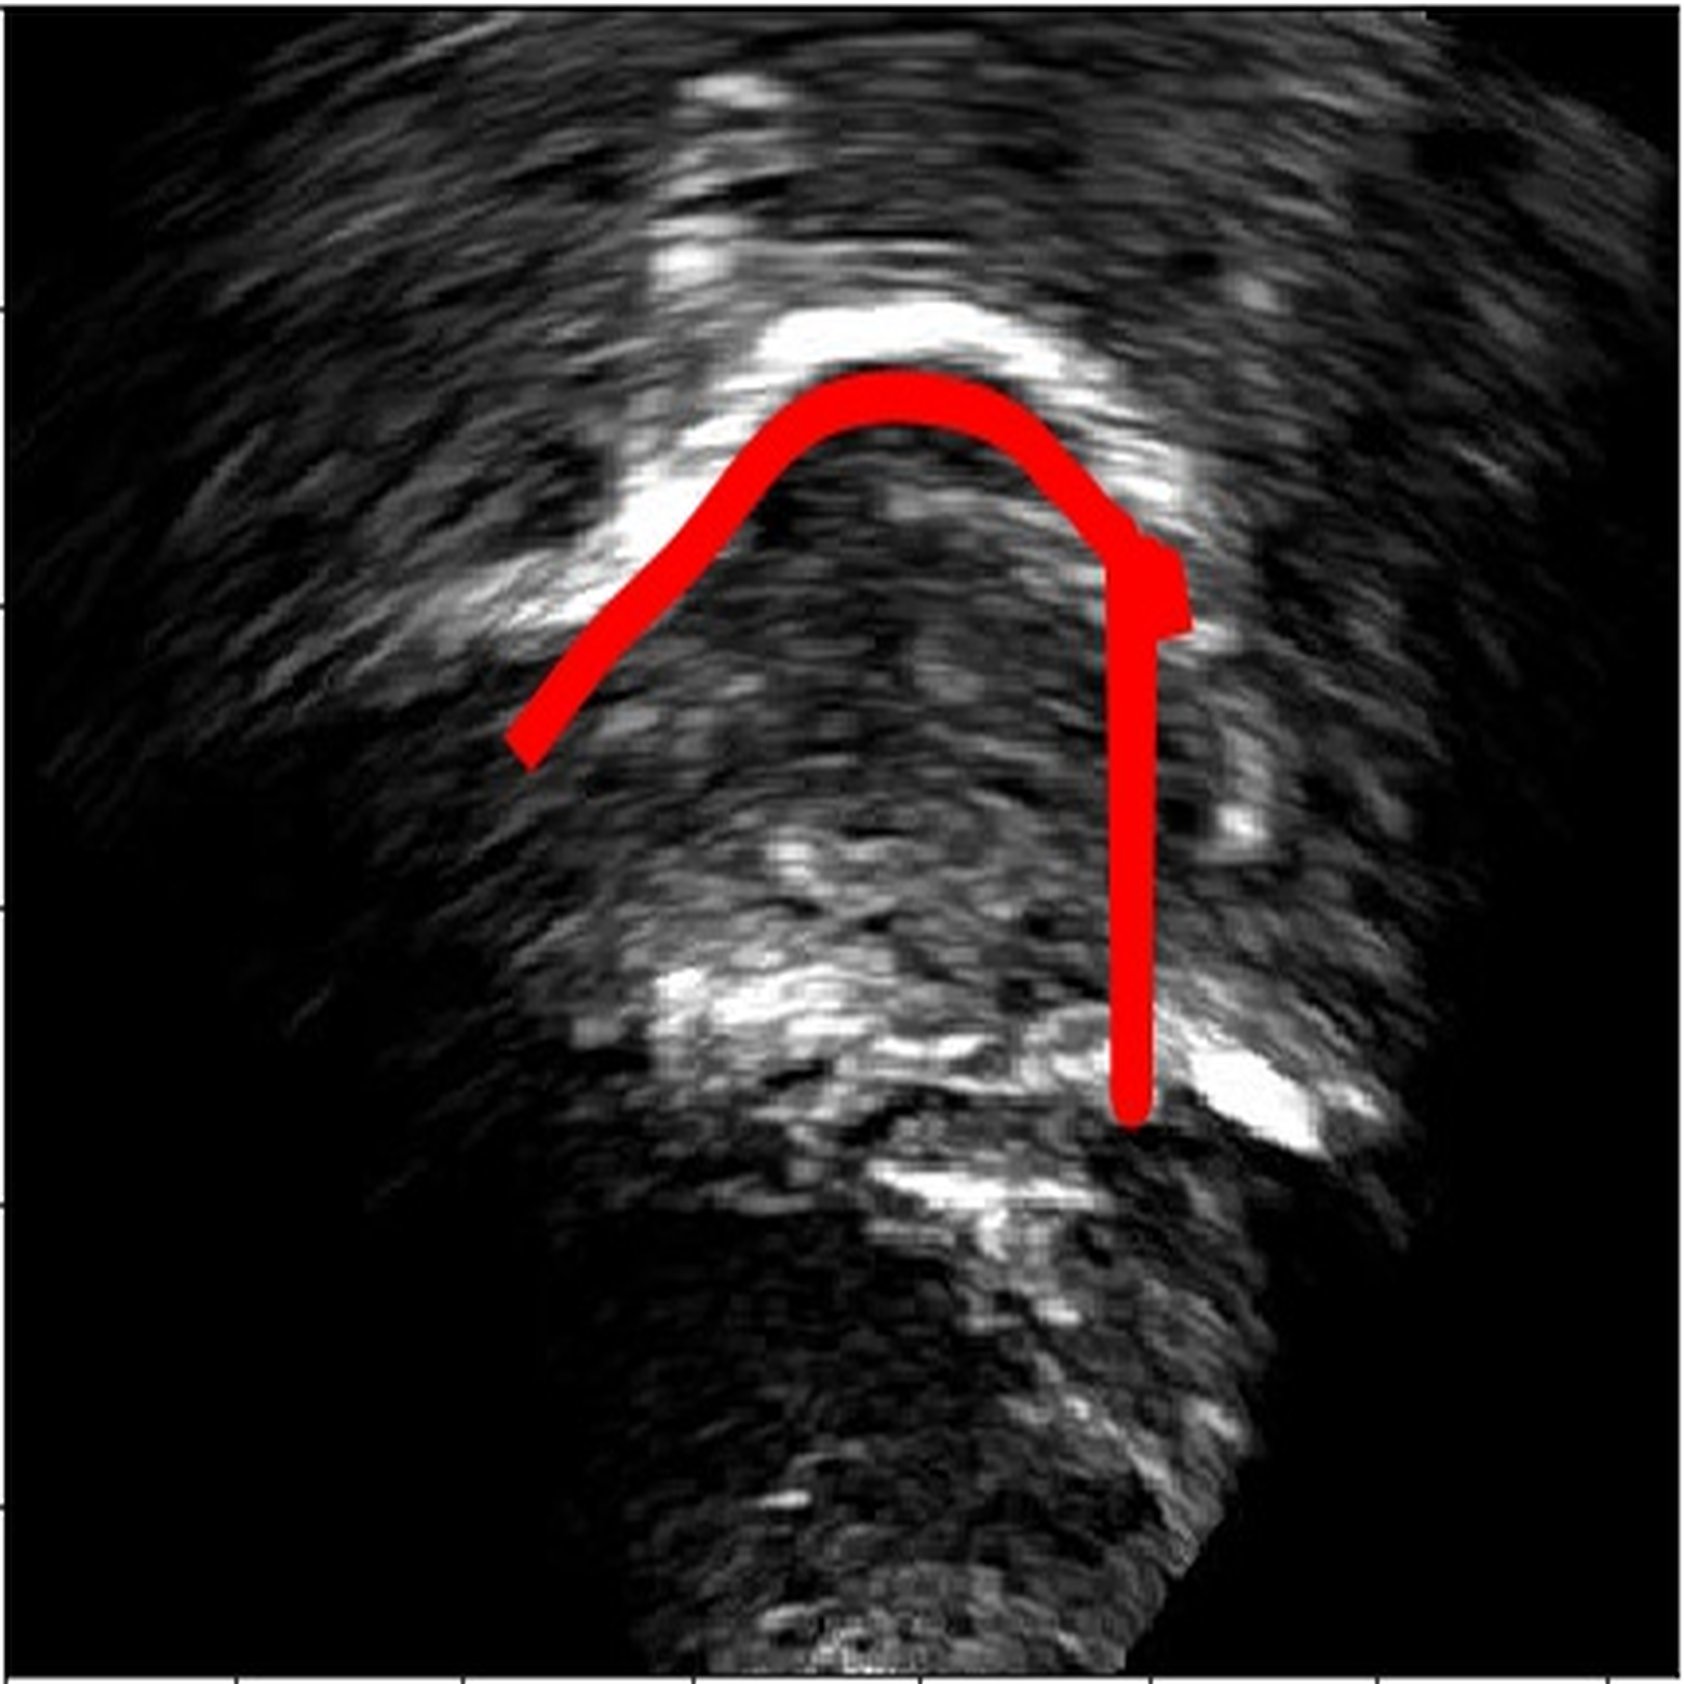

6 Error analysis

As the CNN is trained to identify the white edges directly corresponding to the tongue surface, additional or missing white edges due to bad image quality or speaker physiology can lead to failures in identifying parts of the tongue surface. In the absence of prior knowledge of plausible tongue shapes, the model will sometimes generate tracking errors when the white edge becomes blurry or interrupted. Similarly, bright edges in the image background are likely to be recognized as part of the tongue; tongue contours generated from image frames with these edges will likely suffer from implausible curvatures as interpolation in post-processing attempts to connect these regions. There some potential solutions to these problems, including incorporating temporal constraints on tongue contour variations across frames [3], or adding a smooth constraints that penalizes discontinuity of tongue contours, or introducing a strong prior probability of possible tongue locations. In data processing, these issues can also be mitigated by tuning the parameters in post-processing to match the needs of the specific dataset, and remaining errors can also be addressed through manual correction (as even then, the workload is considerably reduced relative to manually labeling all frames).